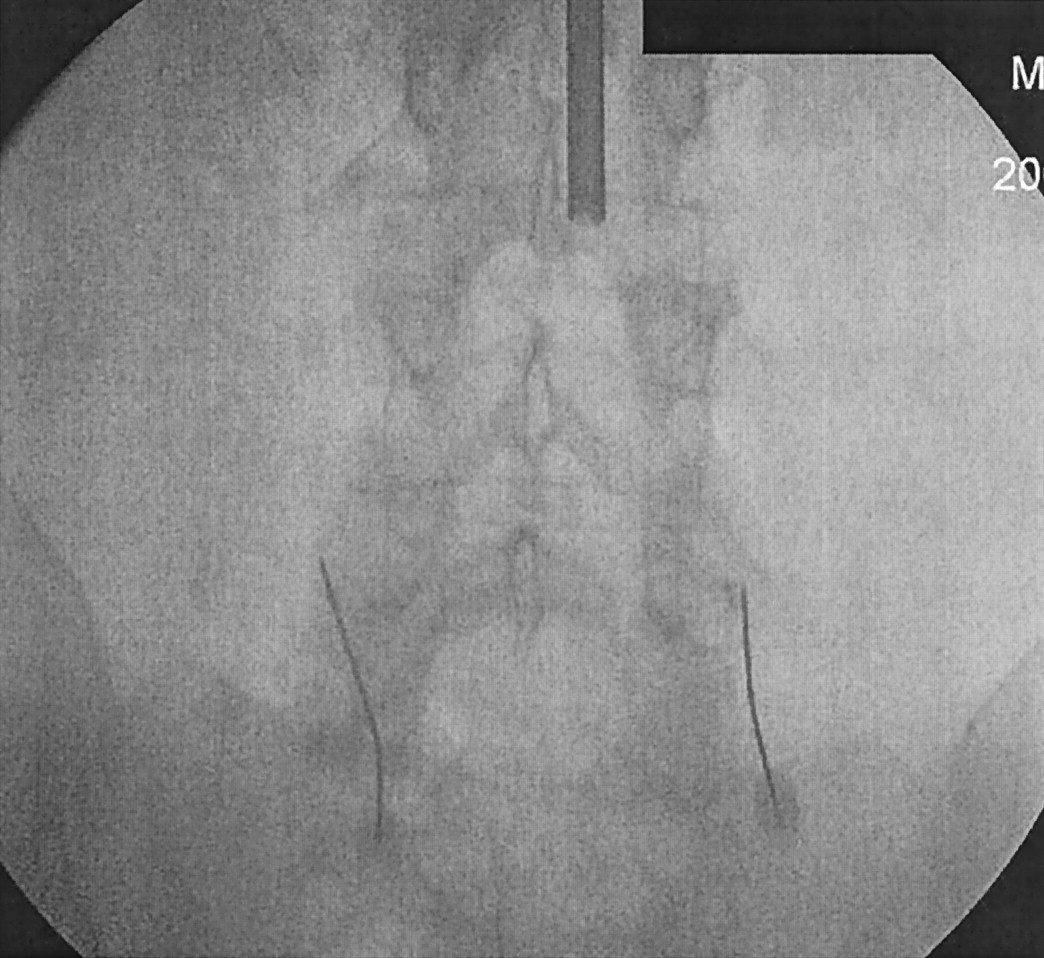

All procedures were performed by the primary author, who is well experienced in both methods. All radiologists and nurses wore protective lead aprons. A spiral CT of the region of interest was done. CT fluoroscopic parameters were chosen (120 kVp, 50 mA). Patients were placed in prone position, and the overlying skin was sterilized. The facet joint was localized using either conventional or CT fluoroscopy. Once localized, a 22-gauge, 3.5-inch needle was directed into the desired facet joint. One needle was used per joint. During CTF, diagnostic accuracy was achieved by ensuring that the position of the tip of the needle was within 5 mm from the superior aspect of the facet of the lumbar spine (Fig 1). For conventional fluoroscopy, the needle tip was placed at the junction between the facet joint and transverse process of the corresponding level (Fig 2). Contrast injections were not used to localize the needles. Once the needles were in place, 1 mL of bupivicane (0.5%) was injected into the joint.

Lumbar facet block at L4–L5 by using CTF.